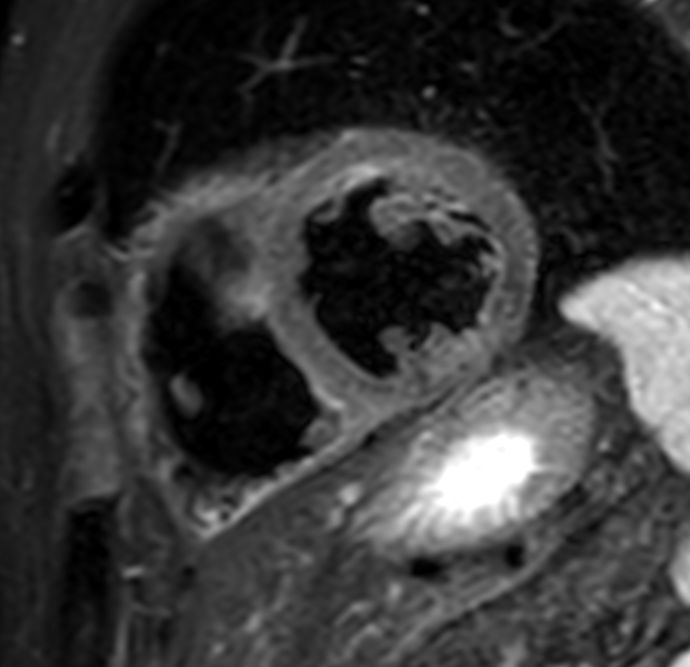

bTFE short axis Without Compressed SENSE: 8.4 sec breath hold